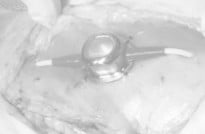

결석은 신장, 요관, 방광, 요도 등 비뇨기 중 어디에도 생성될 수 있습니다. 결석이 비뇨기 폐색을 유발할 경우 아이가 갑자기 뇨를 보지 못하고, 급성 신부전이 발생할 수 있어 응급 수술을 필요로 할 수 있으며, 아이에게 지속적인 불편감을 유발하여 혈뇨, 잔뇨감 등 다양한 임상증상을 나타낼 수 있습니다. 폐색이 유발된 부분, 증상, 재발 여부에 따라 SUB (인공요관우회술) 및 요도를 넓혀주는 수술 등이 필요할 수 있습니다. 본원에서는 내과 및 영상의학과와의 협진과 다수의 비뇨기계 수술 경력의 외과 수의사를 통해 아이에게 필요한 수술법으로 진행하고 있으며, 내과 전담 수의사를 통해 장기적으로 재발 관리 및 모니터링을 지속하고 있습니다.